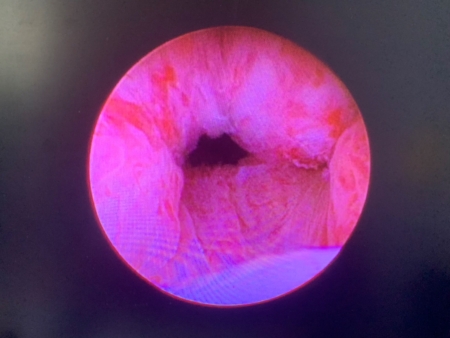

「攝護腺拉開手術」是一種微創、相對安全的新選擇。劉家翔進一步說明,此手術是經由內視鏡,將鎳鈦合金的釘子植入攝護腺肥大的腺體,造成擠壓進而拉開尿路,後續攝護腺組織會因擠壓造成的缺血產生萎縮,尿路即可長期保持通暢;因為手術過程並無加熱切割或是破壞組織,所以不會造成出血、結疤,也不影響射精與勃起功能。